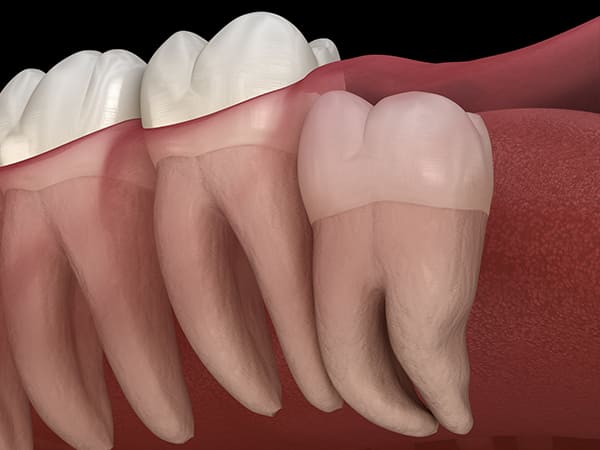

埋もれている水平埋伏の親知らず

歯ぐきの中で完全に真横に生えてしまうタイプです。

この親知らずを水平埋伏智歯と言います。

このタイプは、ほとんどが下顎のケースです。真横に生えているので、抜歯の際は難易度が高く2~3つに砕いて分けて抜歯をします。